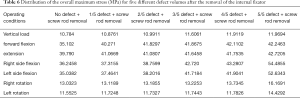

When the removal of the internal fixator was simulated, the stress outcomes of the five types of superior endplate collapse (defect volumes of 1/5, 2/5, 3/5, 4/5, and 5/5 of the anterior-two-thirds edge of the vertebral body, respectively) under vertical load, anteroposterior flexion, lateral flexion, and left and right rotation conditions. The stress distribution maps are shown in Table 6. We also made a table of the stress difference between the two groups in Table 7 and generated a dot plot (Figure 15). It can be seen that with the removal of the internal fixator and the loss of support from the internal fixator as well as the increase in defect volume, the stress gradually grew larger. The dot plot of the difference between groups showed that as the stress increased, the magnitude of change in the combined stress represented by group C (stress difference between the 2/5 defect group and the 3/5 defect group) under the seven working conditions was the largest, suggesting that after the removal of the internal fixator from injured vertebrae with superior endplate collapse and bone defect, when the collapse defect area reached 3/5 of the anterior column of the vertebral body, the concentration of stress increased significantly. This suggests that the risk of continued compression or even refracture of the injured vertebra increases after the removal of the internal fixator.

Full table

Full table